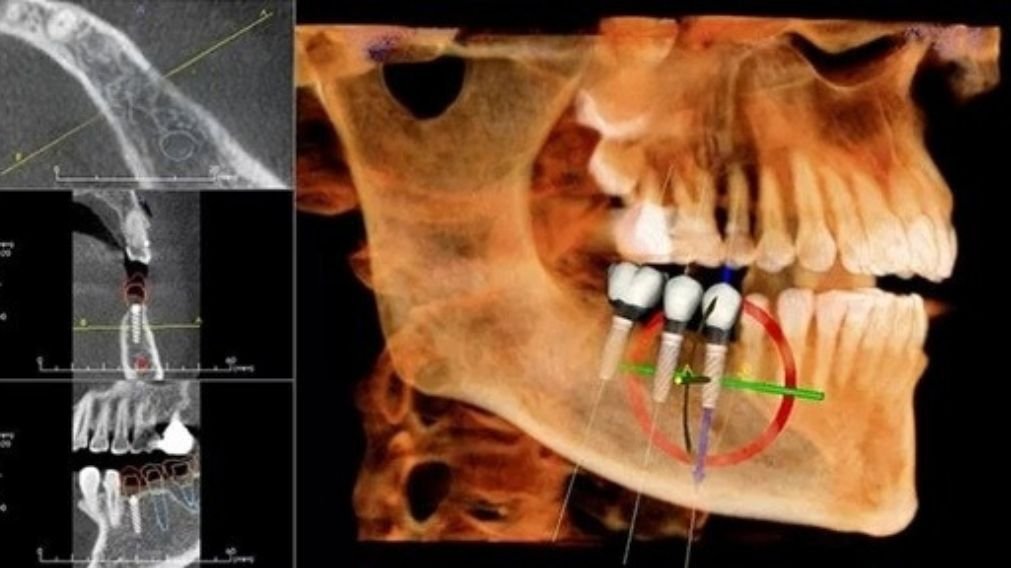

2. Qualidade e Quantidade Óssea Adequada

É preciso ter osso saudável, em altura e espessura suficientes, sem a necessidade de enxerto ósseo, para “abraçar” e travar o implante. A tomografia computadorizada 3D é fundamental para avaliar a densidade óssea e planejar a posição exata do implante, garantindo que ele seja instalado na melhor região óssea disponível.

- Planejamento Digital: O uso de guias cirúrgicas impressas em 3D aumenta a precisão e a segurança, mas adiciona custo.